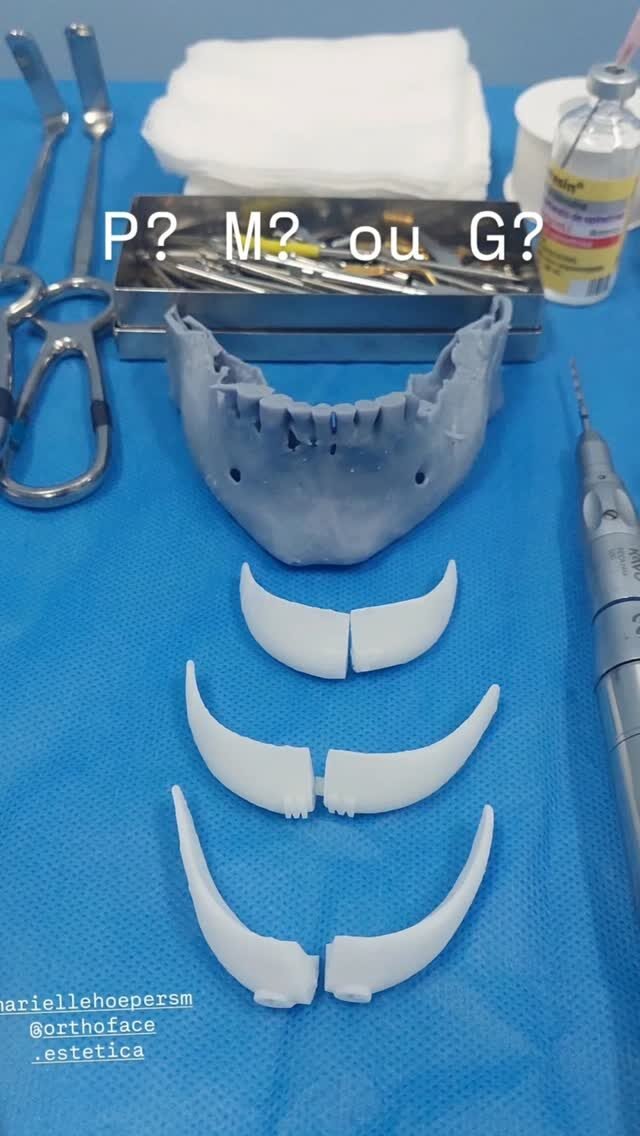

Cirurgia Ortognática

Você sente dificuldade para morder, falar ou até mesmo respirar corretamente? A Cirurgia Ortognática pode ser a solução! Esse procedimento corrige alterações ósseas no maxilar e mandíbula, melhorando a função mastigatória, a harmonia facial e a qualidade de vida.